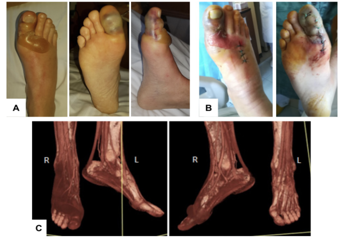

Figure 4: Hypervirulent multidrug-resistant Pseudomonas aeruginosa infection in a neutropenic patient (Coppola et al., 2020)

Skin Lesions

Skin lesions in neutropenic patients may represent evidence of disseminated infection via hematogenous spread and should prompt urgent evaluation.

Figure 16: Skin lesions as evidence of disseminated infection in neutropenic patients